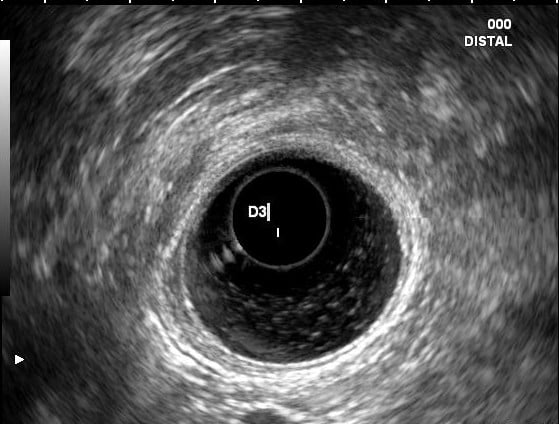

An endoscopic ultrasound (EUS) was performed and showed areas of duodenal wall thickening in D2 and D3, with infracentimetric hypoechoic foci. The pancreatic parenchyma was heterogenous in the pancreatic head and uncinate process, with hyperechoic striae (honeycomb pattern) and hypoechoic lobulations; pancreatic duct was normal.

Figures 2 and 3. EUS showing hypoechoic thickening of the D2 and D3 wall and a hypoechoic foci